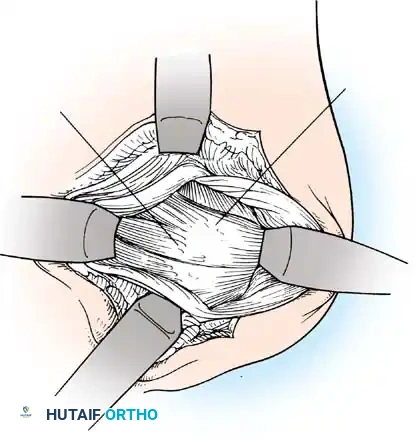

Surgical Approach: The Deltopectoral Interval

- Incision: A standard 5 to 7 cm incision is made starting from the tip of the coracoid process, extending distally and laterally toward the deltoid insertion.

- Superficial Dissection: The cephalic vein is identified within the deltopectoral groove. It is generally retracted laterally with the deltoid to preserve its venous drainage, though medial retraction with the pectoralis major is acceptable if lateral tributaries are sparse.

- Deep Dissection: The clavipectoral fascia is incised lateral to the conjoint tendon (short head of biceps and coracobrachialis). The conjoint tendon is retracted medially. Care must be taken to avoid aggressive medial retraction, which can cause a neurapraxia to the musculocutaneous nerve (typically entering the coracobrachialis 3-5 cm distal to the coracoid).

Subscapularis Management

Exposure of the anterior capsule requires navigating the subscapularis muscle. Historically, a vertical tenotomy was performed; however, modern techniques favor a subscapularis split or a peel to preserve the integrity of the muscle belly and its tendinous insertion.

Capsulotomy and Joint Inspection

- A Fukuda retractor is placed within the joint to retract the humeral head laterally and posteriorly, exposing the anterior glenoid rim and labrum.